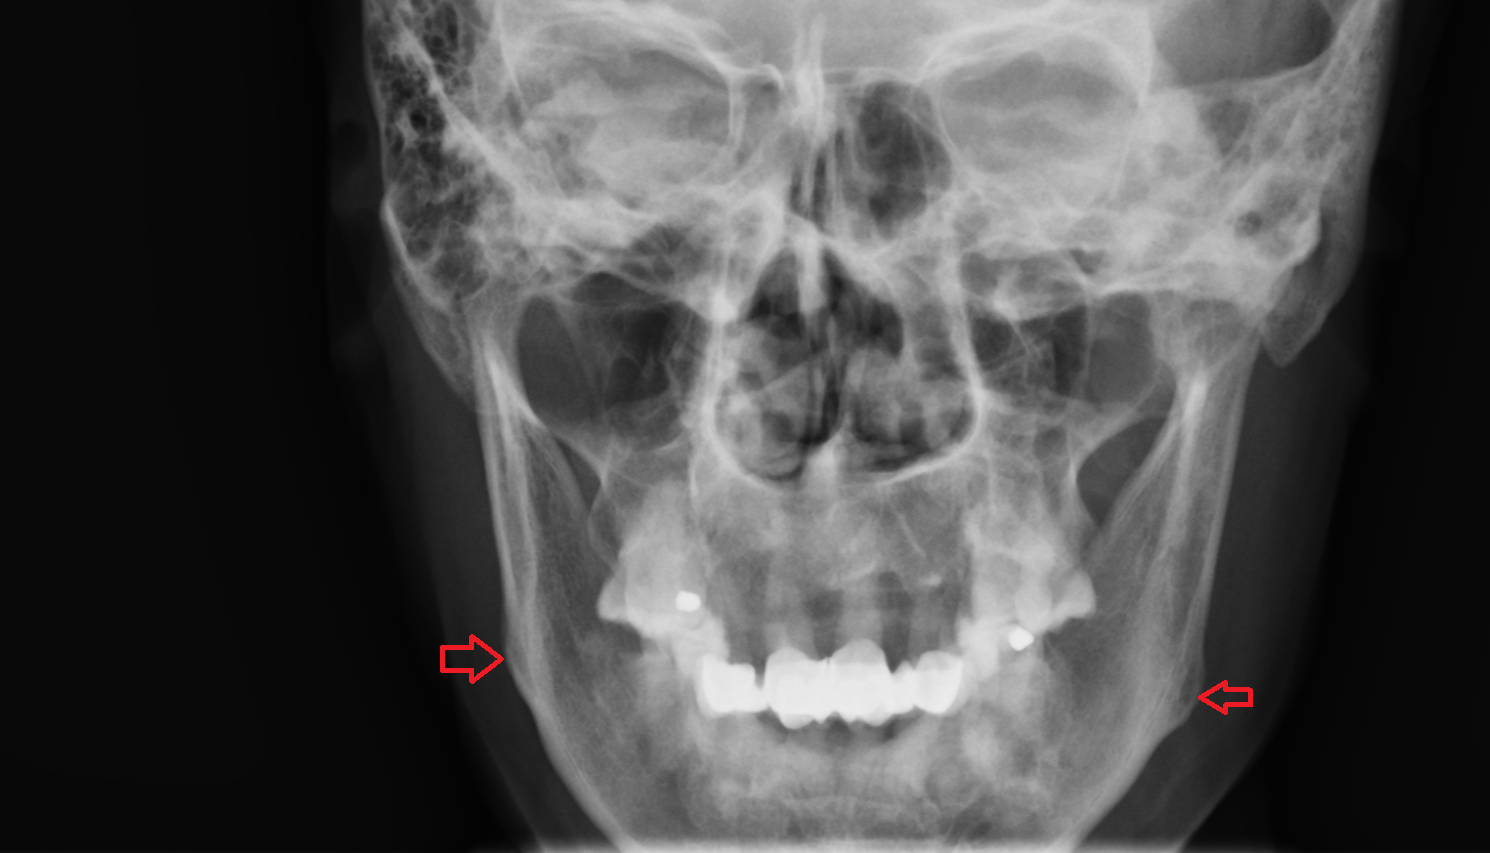

- Carotid bifurcation

- Common carotid artery

- External carotid artery

- Internal carotid artery (cervical part)

- Mandibular canal

- Mental foramen

- Inferior alveolar foramen (mandibular foramen)

- Mandibular foramen